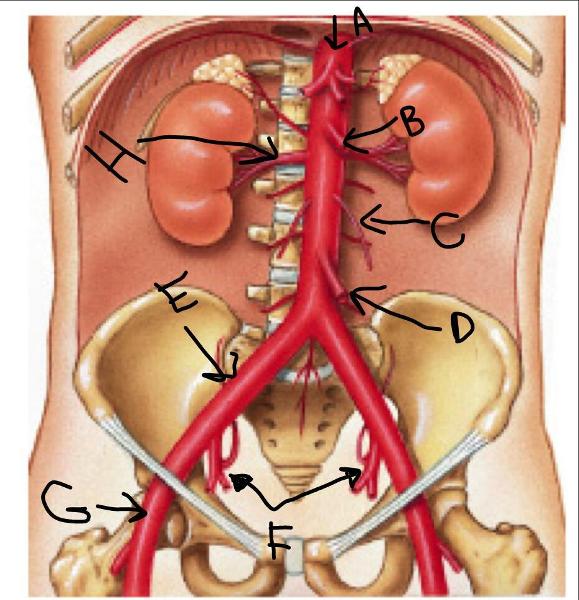

Abdominal Aorta

Common iliac artery/vein

Internal/external iliac artery/vein

Gonadal (=testicular/ovarian) artery/vein

Superior/inferior mesenteric artery

Renal artery/vein

D

H

G